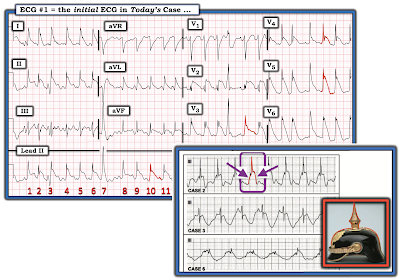

An acutely ill man in his 40s was admitted to the hospital. Suffice it to say that the patient was intubated — and that there was multi-organ involvement including effects from severe alcoholism, mental confusion, tenuous fluid balance — and significant ventricular dysfunction on Echo. His initial ECG is shown in Figure-1.

The rhythm in ECG #1 is sinus at a rate of 90-95/minute (ie, a small but definitely-present upright P wave is seen in lead II — and negative sinus P waves are consistently seen in leads V1 and V2).

- Regarding Intervals: The PR interval is normal — and the QRS complex is narrow — but the QTc is markedly prolonged (especially in the lateral chest leads — the QT takes up ~2/3 of the R-R interval!).

- Small (probably insignificant) q waves are seen in multiple leads (ie, leads I,II,III,aVF; V4,V5,V6). R wave progression is slightly delayed (Transition, where the R wave becomes taller than the S wave is deep — occurs between leads V4-to-V5).

- ST-T wave appearance is remarkable, in that ST segments are coved (although not significantly elevated) in multiple leads — with diffuse, wide and extremely deep T wave inversion.

- Especially in leads V4,V5,V6 (but also in several limb leads) — I found it difficult to determine where the baseline was!

My IMPRESSION of ECG #1: Sinus rhythm — a narrow QRS, but markedly prolonged QTc interval — diffuse ST segment coving (but probably not significant ST elevation) accompanied by wide and deep, symmetric T wave inversion — with a highly unusual picture in which it is difficult to determine where the baseline is.

- Starting with what ECG #1 is "not" — I did not interpret this tracing as suggestive of acute infarction.

- Instead — the marked QTc prolongation — with diffuse ST-T wave abnormalities (ST coving; deep, wide and symmetric T wave inversion) that are not attributable to any specific anatomic area is highly suggestive of Takotsubo Cardiomyopathy (See ECG Blog #46 — for full discussion of this entity). The acutely ill state of today's patient, together with the report of significant ventricular dysfunction on Echo could certainly be consistent with Takotsubo (Clearly — specifics of the Echo would be needed to determine if the findings were or were not diagnostic of Takotsubo).

- BOTTOM LINE: In addition to suspicion about Takotsubo Cardiomyopathy — I thought ECG #1 was strongly suggestive of the Spiked Helmet Sign.